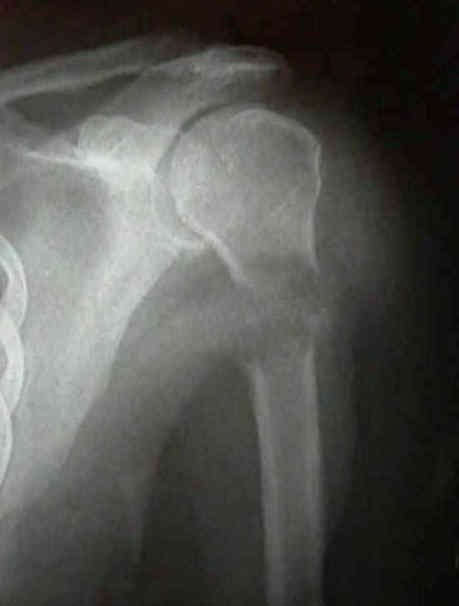

Metástasis óseas trauma .

Enfermedad metastásica ósea: Diagnóstico y tratamiento .

Lesiones tumorales y pseudotumorales del esqueleto ... .

- 4) METSTASIS .

REACCIONES DEL HUESO FRENTE AL ESTRES: ESTUDIO RADIOLOGICO .